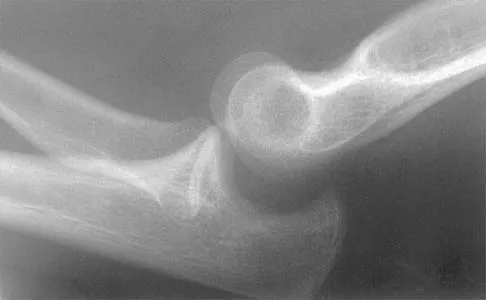

Test your knowledge with updated Orthopedic MCQs for 2026. Perfect for board exam preparation, FRCS, and Prometric test practice.